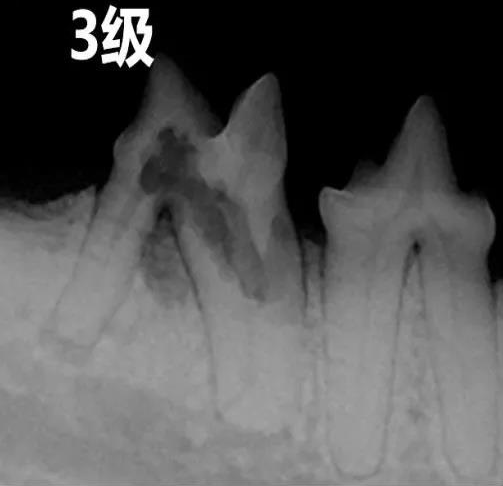

牙吸收病基于影像学分型——分为1型,2型,3型

3级

牙吸收病影响到牙髓腔, 出现髓腔吸收